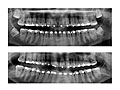

Teeth

Your dentist will check for signs of a wisdom tooth coming through your gum or crowding other teeth. You will have X-rays to find out if your wisdom teeth are causing problems now or are likely to cause problems in the future.